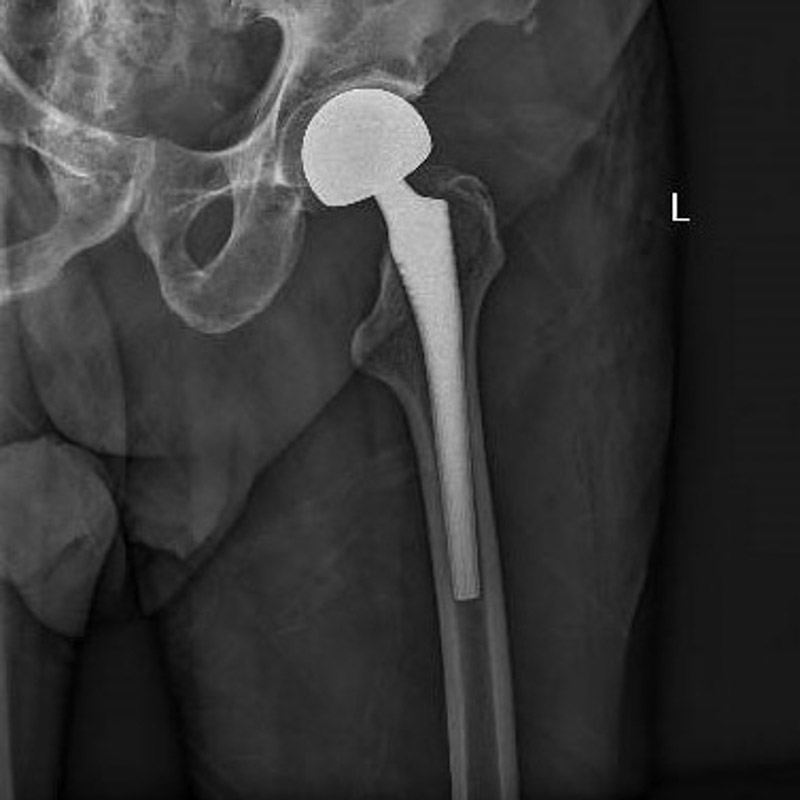

经过周密的术前准备,6月30日,在麻醉科团队成功实施腰椎管内麻醉后,创伤骨科团队为患者进行左侧人工股骨头置换术,手术过程顺利。术后罗老伯恢复良好,围术期内无心肌缺血症状发作,监测心电图无动态改变。